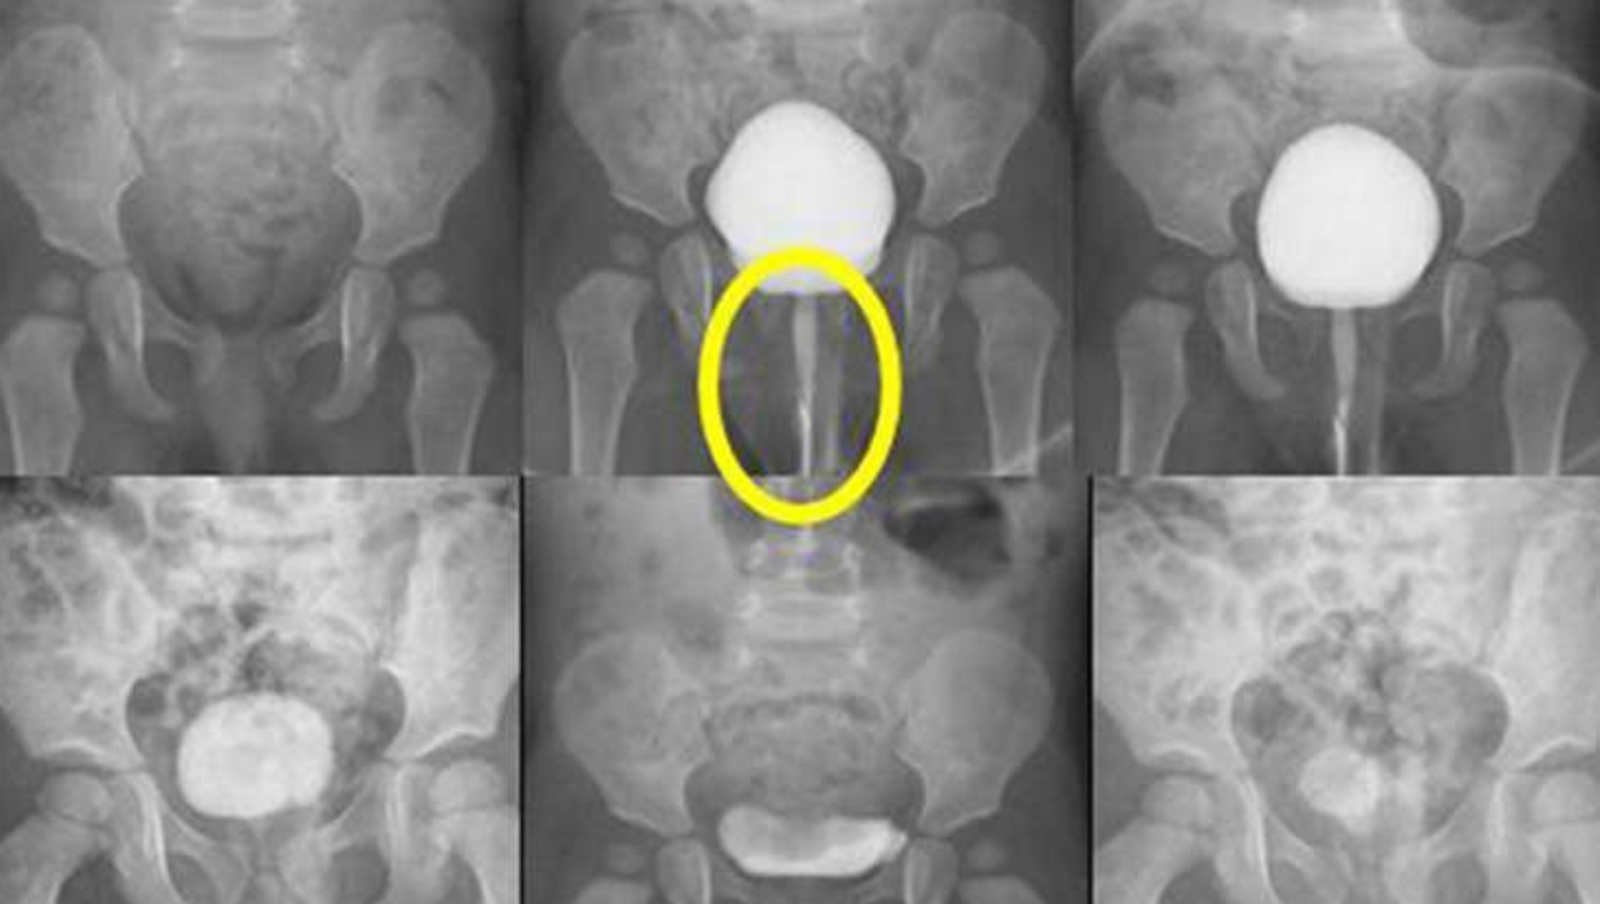

O que é uma uretrocistografia?

uretrocistografia

Uretrocistografia – No mundo complexo da medicina diagnóstica, como podemos realmente entender o funcionamento das técnicas que visam explorar o interior do corpo humano sem procedimentos invasivos? A uretrocistografia, embora desconhecida para muitos, desempenha um papel crucial na avaliação de certas condições urológicas. Este exame é amplamente utilizado para investigar e tratar diversas patologias do trato … Ler mais